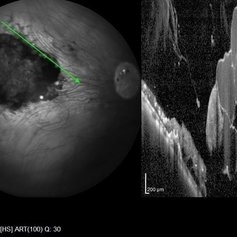

Choroidal Melanoma

Optical coherence tomography with enhanced depth imaging of a 78-year-old female with choroidal melanoma with subretinal fluid affecting her right eye.

Photographer: Olivia Rainey

Imaging device: Heidelberg Spectralis

Condition/keywords: enhanced depth imaging, infrared image, optical coherence tomography (OCT), subretinal fluid, superior retina